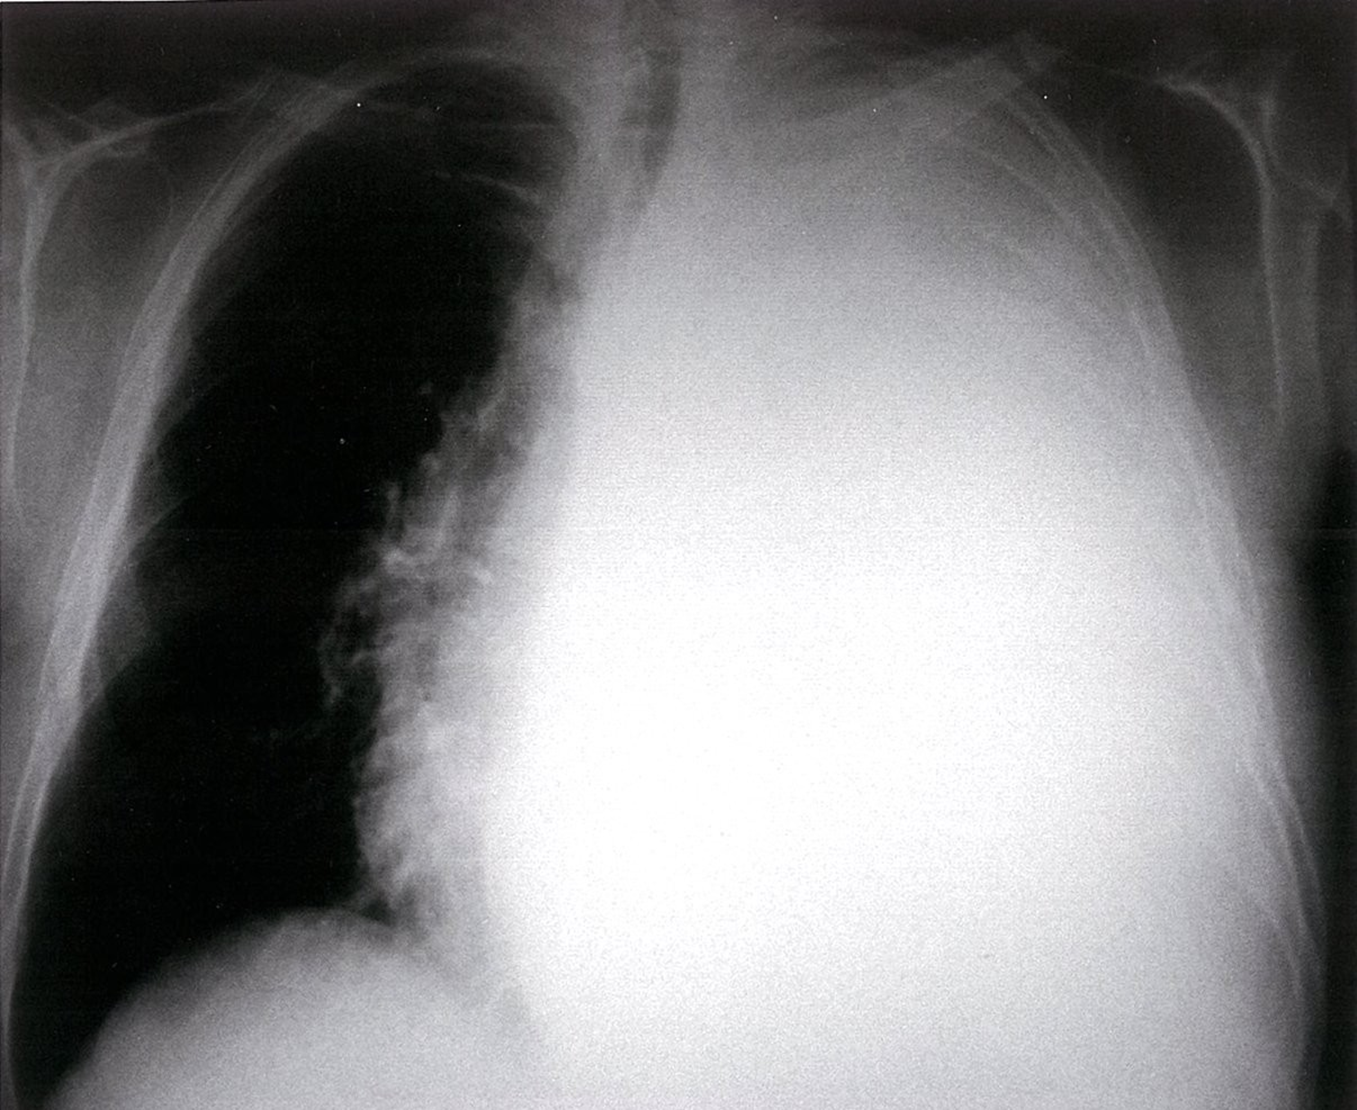

What is your diagnosis? Tension Pneumothorax

Left Sided Massive Pleural Effusion with Mediastinal Shift